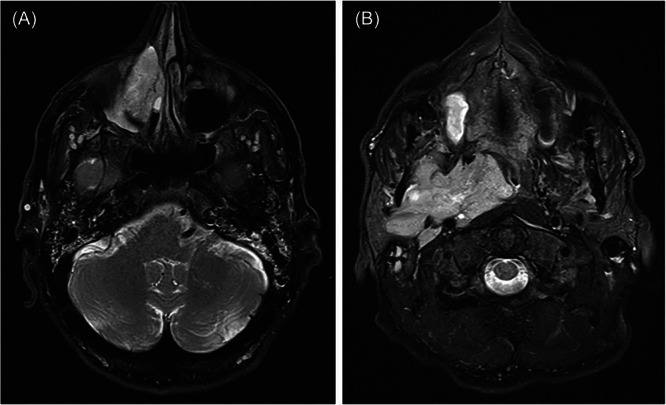

Epistaxis and Trismus Unmasking Metastatic Nasal Cavity Mucosal Melanoma Involving the Parapharyngeal Space.

鼻出血和鼻衄揭示转移性鼻腔黏膜黑色素瘤累及咽旁间隙。